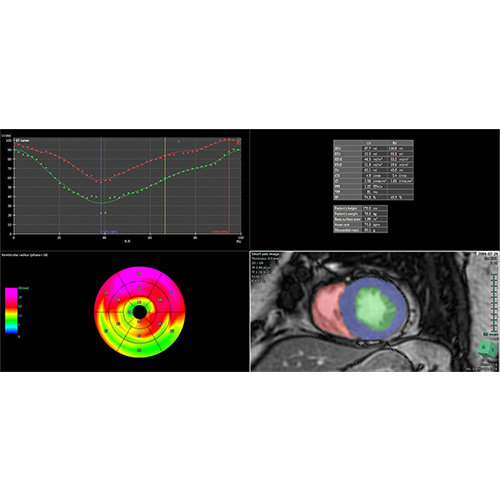

View X-Ray CT & MRI Scans Fast and Easily

Designed for surgeons, Pro Surgical 3D makes it easy to view patient scans quickly. Pro Surgical 3D facilitates the optimal 3D treatment and assessment workflows based on X-ray CT and MRI scans – and best of all, it’s FREE!

High-quality and fast 3D reconstruction and 3D rendering

Designed mainly for CT and MR DICOM modalities.

Performs 3D reconstruction and volume rendering.